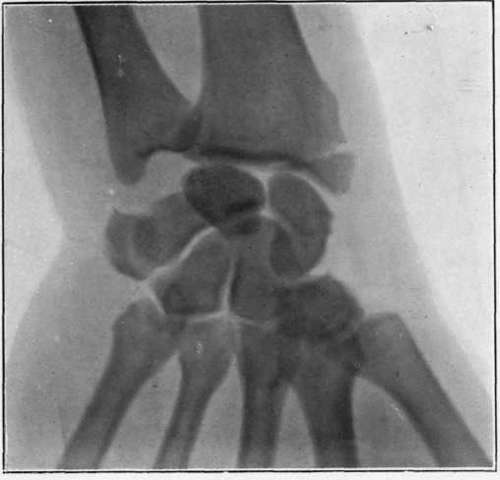

Plate VII.

Fig. I. - ' Motor sprain ' of wrist. Separation of styloid process of radius, caused by attempt at starting the engine of a motor car. Fracture discovered by use of x-rays some time after the injury.